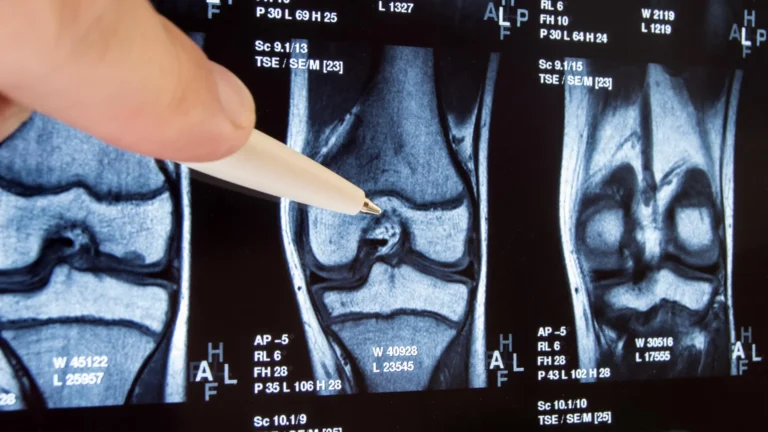

The King’s College London study sought to bridge this knowledge gap by systematically examining the biochemical alterations occurring in patients’ blood following successful root canal procedures. The research team recruited sixty-five individuals undergoing treatment at the Guy’s and St Thomas’ NHS Foundation Trust, subjecting them to a comprehensive two-year follow-up period. Throughout this observational phase, scientists employed sophisticated analytical techniques, including nuclear magnetic resonance (NMR) spectroscopy, to scrutinize a wide array of molecules circulating within the patients’ bloodstreams. This advanced methodology enabled a detailed understanding of how the body metabolizes essential substances such as glucose and lipids, and crucially, how it responds to the presence of infection and the subsequent therapeutic intervention.